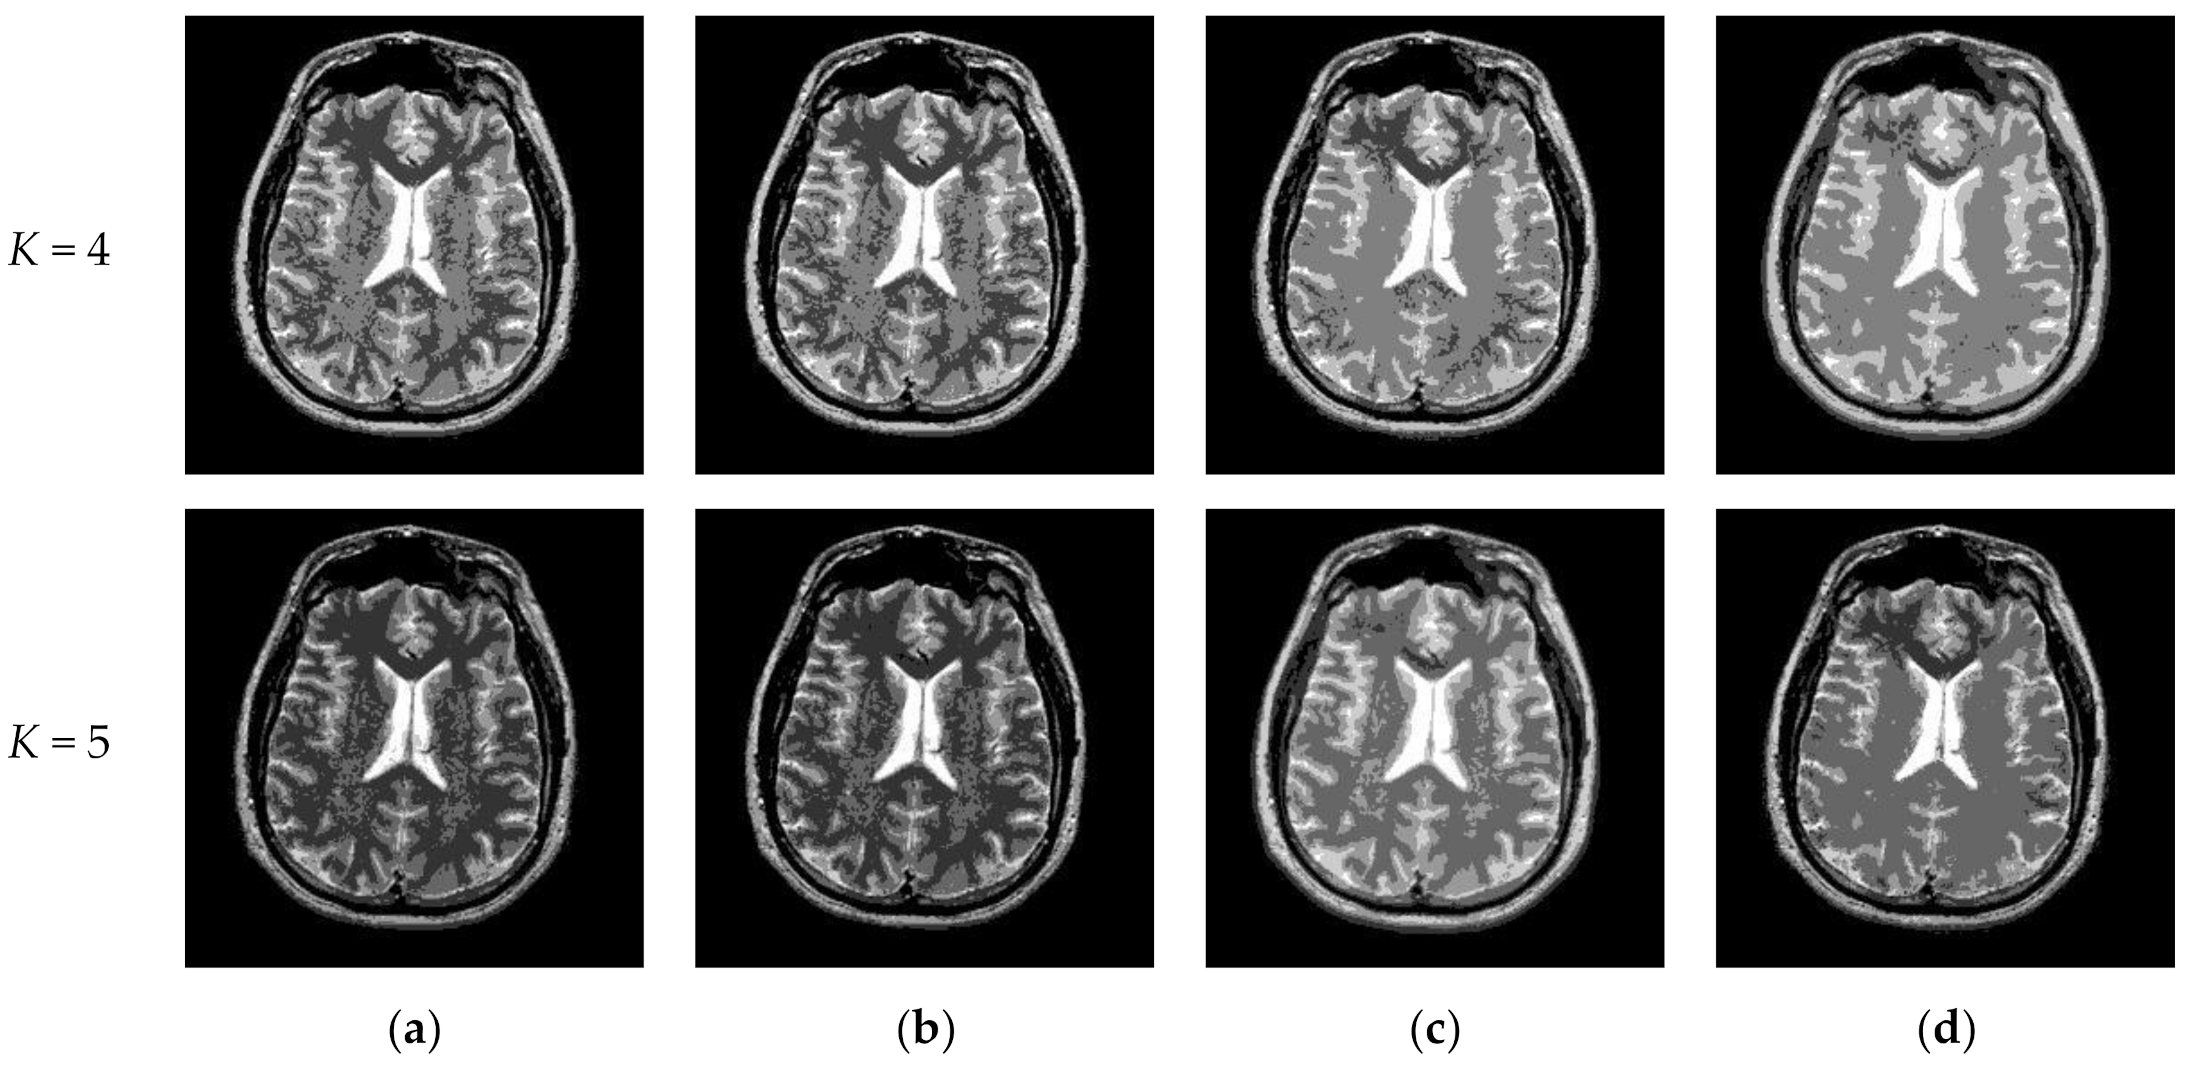

Figure 10 and Figure 11 display segmentation results of different algorithms for slice #042 and slice #082, respectively. For single level of thresholding K = 1, it can be observed that segmentation results obtained by the Otsu method have many fragmented small areas, such as the lower soft tissue in the first row of Figure 10a, whereas IIMT performs slightly better. However, the edges segmented by HL-IIMT and Proposed are much clearer. In the case of , it can be seen that Otsu and IIMT have similar segmentation effects. HL-IIMT and Proposed are better than Otsu and IIMT in terms of edge-preserving and denoising, as shown in the segmentation results in Figure 11 (K = 2, K = 4).

Figure 10.

Segmentation results obtained by different segmentation algorithms for slice #042 with number of thresholds K from 1 to 5: (a) Otsu, (b) IIMT, (c) HL-IIMT, (d) Proposed.

Figure 11.

Segmentation results obtained by different segmentation algorithms for slice #082 with number of thresholds K from 1 to 5: (a) Otsu, (b) IIMT, (c) HL-IIMT, (d) Proposed.